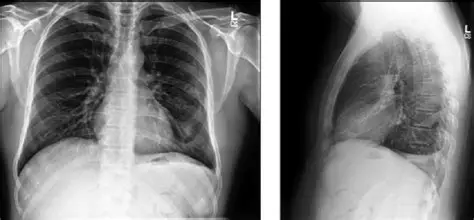

1. CheXpert Plus:肺病诊断的 “X 光图库”

什么是 CheXpert Plus?

在医院拍胸片后,AI 系统能快速提示 “可能有肺炎”,这背后就是 CheXpert Plus 这类医学数据集在工作。

它是斯坦福大学整理的胸部 X 光数据集,包含:

- 22 万 + 张胸片,来自 6 万多名患者;

- 每张片子都有医生标注的诊断结果(比如 “肺炎”“肺结核”“正常”);

- 覆盖从儿童到老人的不同年龄段。

为什么它能辅助医生诊断?

医学数据的标注需要极强的专业性,CheXpert Plus 的优势在于:

- 标注权威:由放射科医生审核,确保诊断结果准确;

- 覆盖全面:包含早期轻微病变(容易被忽略的小问题);

- 关联临床:每张片子都关联患者的年龄、症状等信息。

应用案例:阿里健康的 “胸部 X 光 AI 辅诊”

阿里健康 2025 年在全国 100 家基层医院部署的 AI 辅诊系统,用 CheXpert Plus 训练后,对肺炎的识别准确率达到 96%,比基层医生的平均水平高 15%,尤其适合医疗资源不足的地区。